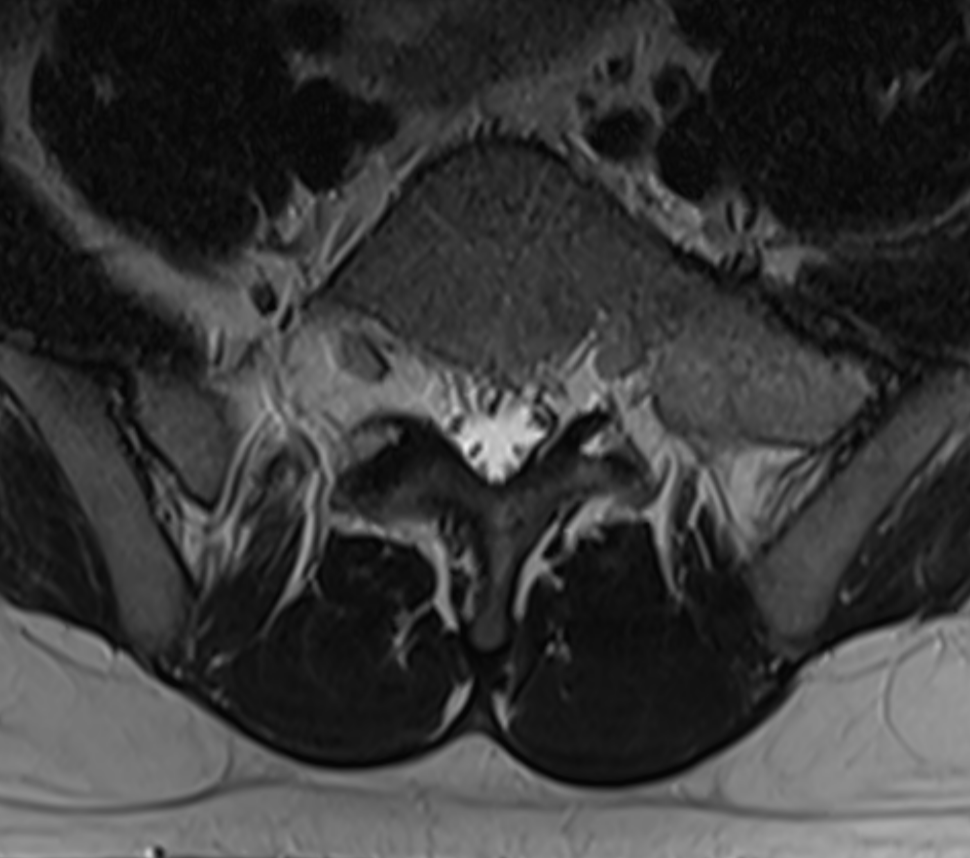

3. Transitional vertebra L5 - Bertolotti Syndrome